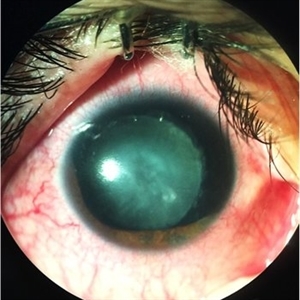

Blunt Trauma

May 18 2016 by Andrea Arriola-Lopez, MD MSc

26-year-old man, old ocular blunt trauma. VA HM OD. IOP 14mmHg. Traumatic partial aniridia, cataract and phacodonesys. Ophthalmoscopy showed diffuse hemovitreous, Retina remained attached.

Photographer: Andrea E. Arriola-López MD MSc

Condition/keywords: aniridia, cataract, trauma, traumatic cataract